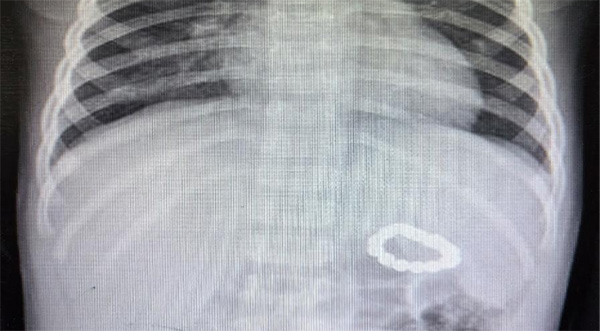

2岁的小明(化名)因上呼吸道感染就诊于当地医院,行胸片检查发现消化道金属异物,保守治疗随诊观察后复查异物位置无变化。但几天后,家长带小明来到北京儿童医院就诊,行急腹症超声提示胃内异物与横结肠异物,相互吸引形成一个闭环,怀疑胃肠穿孔。

术中,消化科秦秀敏副主任医师凭借丰富的经验和精湛的操作技巧,先后从小明的胃及结肠取出了13枚磁力珠异物,并顺利在内镜下进行了穿孔创面止血封闭,术后复查腹片提示异物全部取出且恢复良好。小明家长对全体医护表达了衷心的感谢。